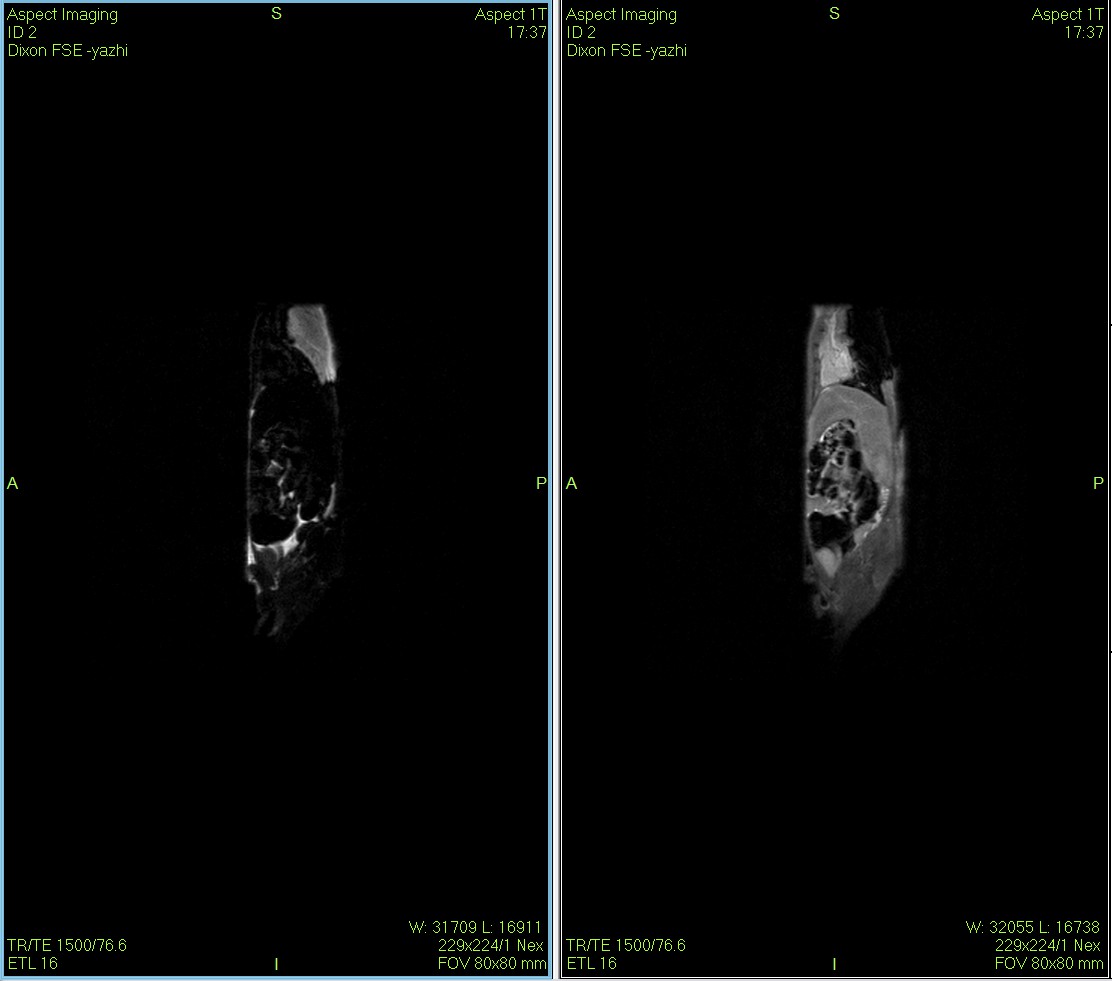

Dixon脂肪抑制技術是由Dixon 提出,其基本原理是利用水、脂肪的化學位移差異,使用不同的回波時問,分別采集水和脂肪質子的in Phase 和 opposed -phase兩種回波信號。